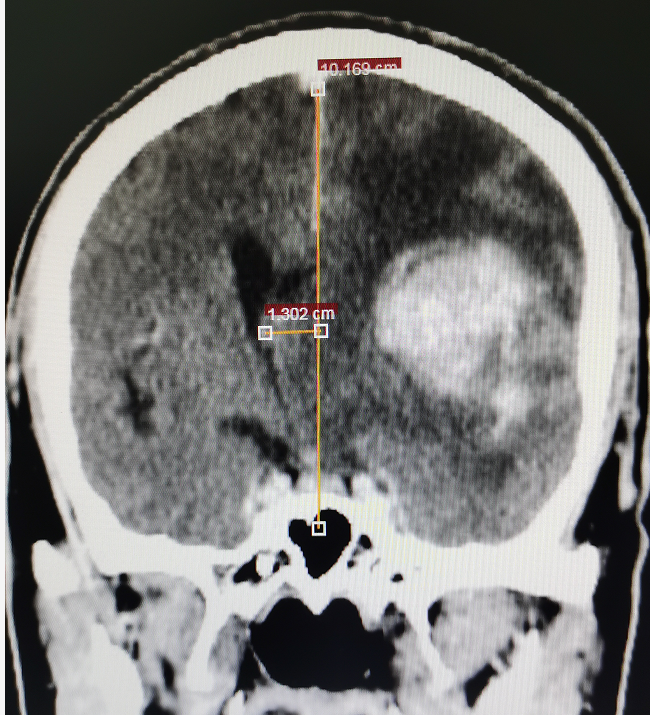

62岁的陈先生于今年曾因偏瘫在外院住院治疗无好转,且症状不断加重,甚至出现言语不清,小便失禁等异常。经影像检查(见图1)提示为左颞叶基底节区脑肿瘤,约6cm*5cm*5cm大小,比鹅蛋还要大,肿瘤位置深,向前累及外侧裂,包裹外侧裂部分血管,向下累及基底节区,肿瘤血供丰富,必须尽早实施手术治疗。

术前影像资料及手术标本,术前见中线结构严重偏移,侧脑室受压缩小,肿瘤周围水肿严重,肿瘤血供丰富